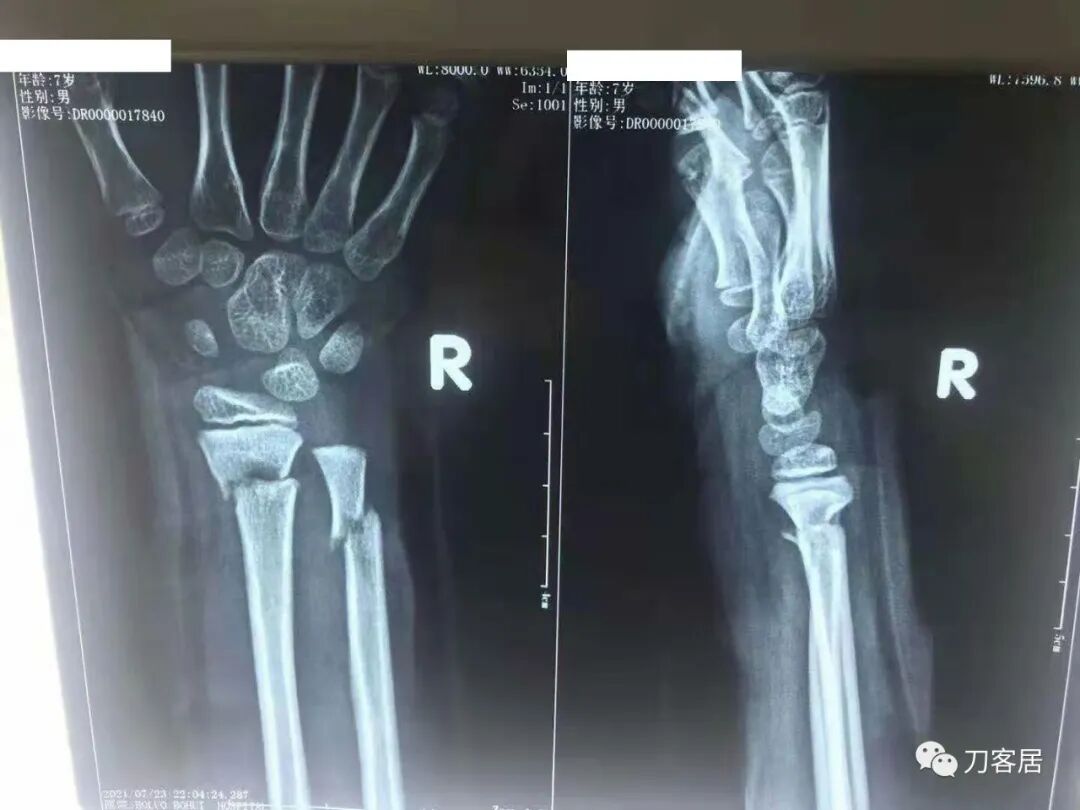

下面为师东良医生提供的病例:

超声引导下闭合手法复位石膏外固定治疗7岁患儿尺桡骨远端移位双骨折。

男,7岁,左前臂远端桡尺骨双骨折,术前X光片见图1,行超声引导下闭合复位石膏外固定术,康复训练,6周拆石膏,随访2.5月的效果。术后2.5X光片见图23。功能上仅前臂旋后较健侧减小15°,继续加强康复训练中。家长满意,评价见图4

1. 超声引导下闭合复位石膏外固定术左尺桡骨双骨折

2. 超声引导下闭合复位石膏外固定术后2.5月左前臂正位X光片

3. 超声引导下闭合复位石膏外固定术后2.5月左前臂侧位X光片